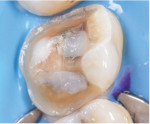

Regarding the assessment of clinical outcomes of restorative procedures, it is of paramount importance for clinicians to realize that the longevity of the tooth is a more accurate metric than the longevity of the restoration. Conservative preparations protect teeth from the trauma caused by the excessive use of rotary instrumentation (Figure 3 and Figure 4).

To maximize the longevity of partial-coverage restorations, their preparations should be designed with simple geometry that includes all of the defective areas but does not involve any abrupt transitions (Figure 5). Proper reduction is key (Figure 6). Preparation designs for partial-coverage restorations are material dependent; therefore, the manufacturer's recommendations should always be followed. Generally, contemporary ceramics are required to be at least 1.0-mm to 1.5-mm thick when bonded using adhesive resin cements.

Regarding preparation design, the walls of preparations for partial-coverage restorations should be divergent to allow for path of insertion and have rounded angles to facilitate stress distribution. To develop a durable and long-lasting bond, the presence of enamel 360 degrees around the preparation's supragingival margin is essential (Figure 5). When assessing cuspal involvement, the preparation should include any cusp with a remaining thickness of less than 2 mm (Figure 7 and Figure 8). This is critical to maintain the integrity of the tooth and, subsequently, the restoration.